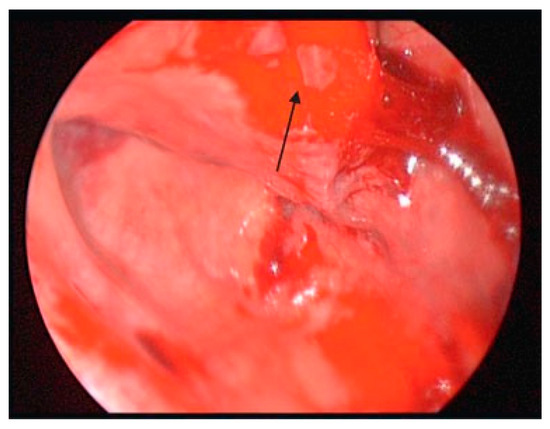

Figure 9. Uncinate to the left upfront, bulla taken down, and the anterior ethmoid exposed.